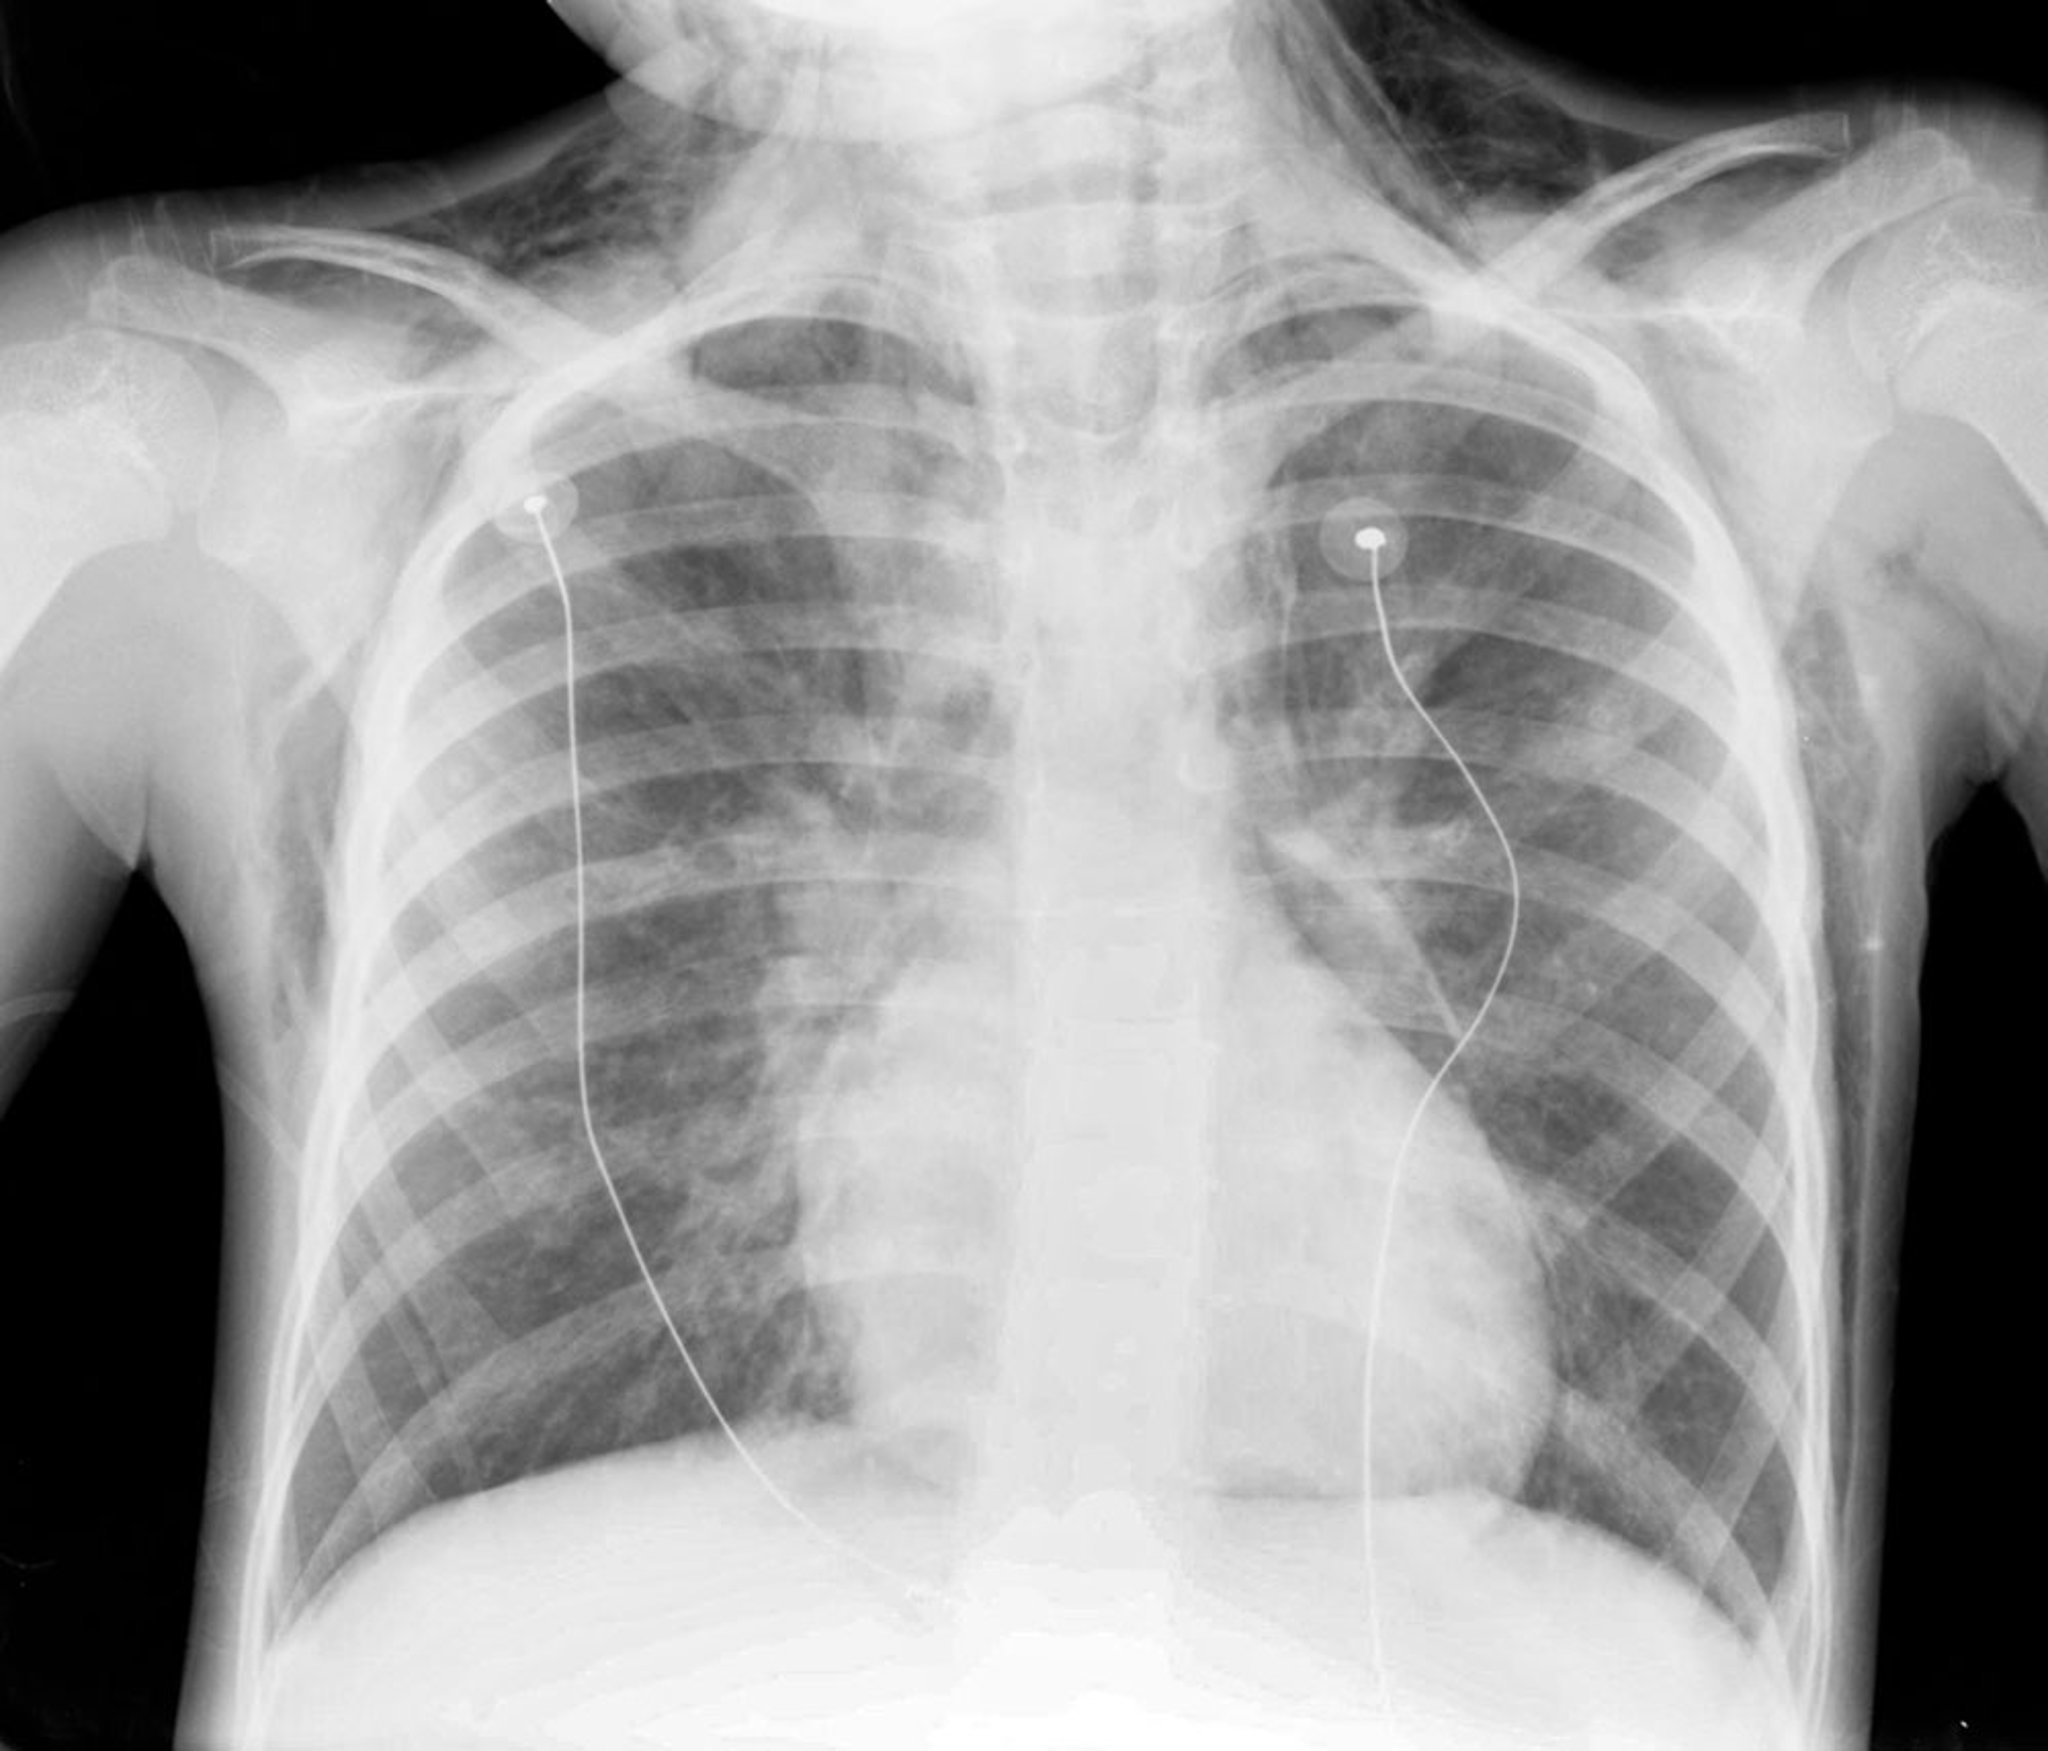

Chẩn đoán được xác nhận bằng phim chụp X-quang ngực, cho thấy có khí ở trung thất.